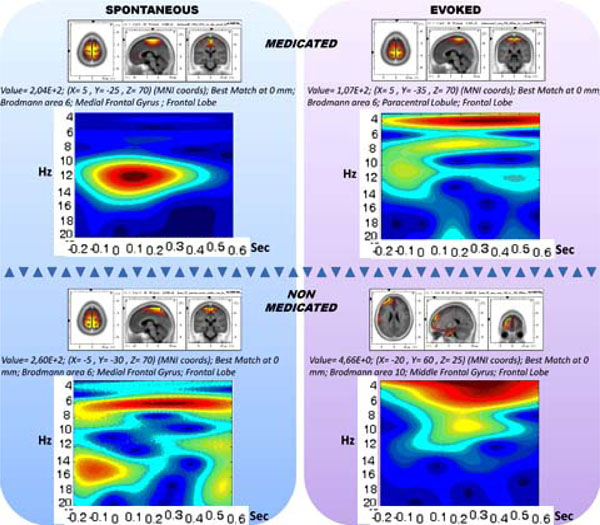

Medicated/Non-Medicated vs. Evoked/un-evoked Activity

The medication and evoking changes in the sLORETA and spectrogram are provided in Fig. (6). The medicated and non-medicated sections are displayed in columns and unevoked vs. evoked activity are provided in rows. Accordingly, the drug-free panel has a spectrogram with a wide range of activity of (0.5-25 Hz), whereas the medication enforces spindle oscillations (11-14 Hz). When the stimulations are presented, the non-medicated wide range activity narrows down towards delta and theta activity. The spindle oscillations, however, were enforced towards slower oscillations partially breaking down the mono-frequency entrainment. Table 1 displays the CDV of the two groups.

The 2X2 representation of spectrograms and sLORETAs for medicated (horizontal upper), non-medicated (horizontal lower) vs. un-evoked spontaneous (vertical left) and evoked (vertical right) conditions.